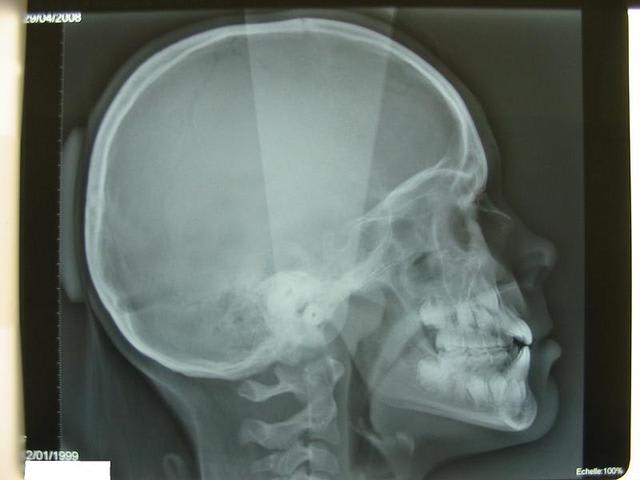

07/05/2009 à 15h56

ci joint la télé, pour les photo il va falloir attendre le prochain rdv

Img p e b10lw9 - Eugenol